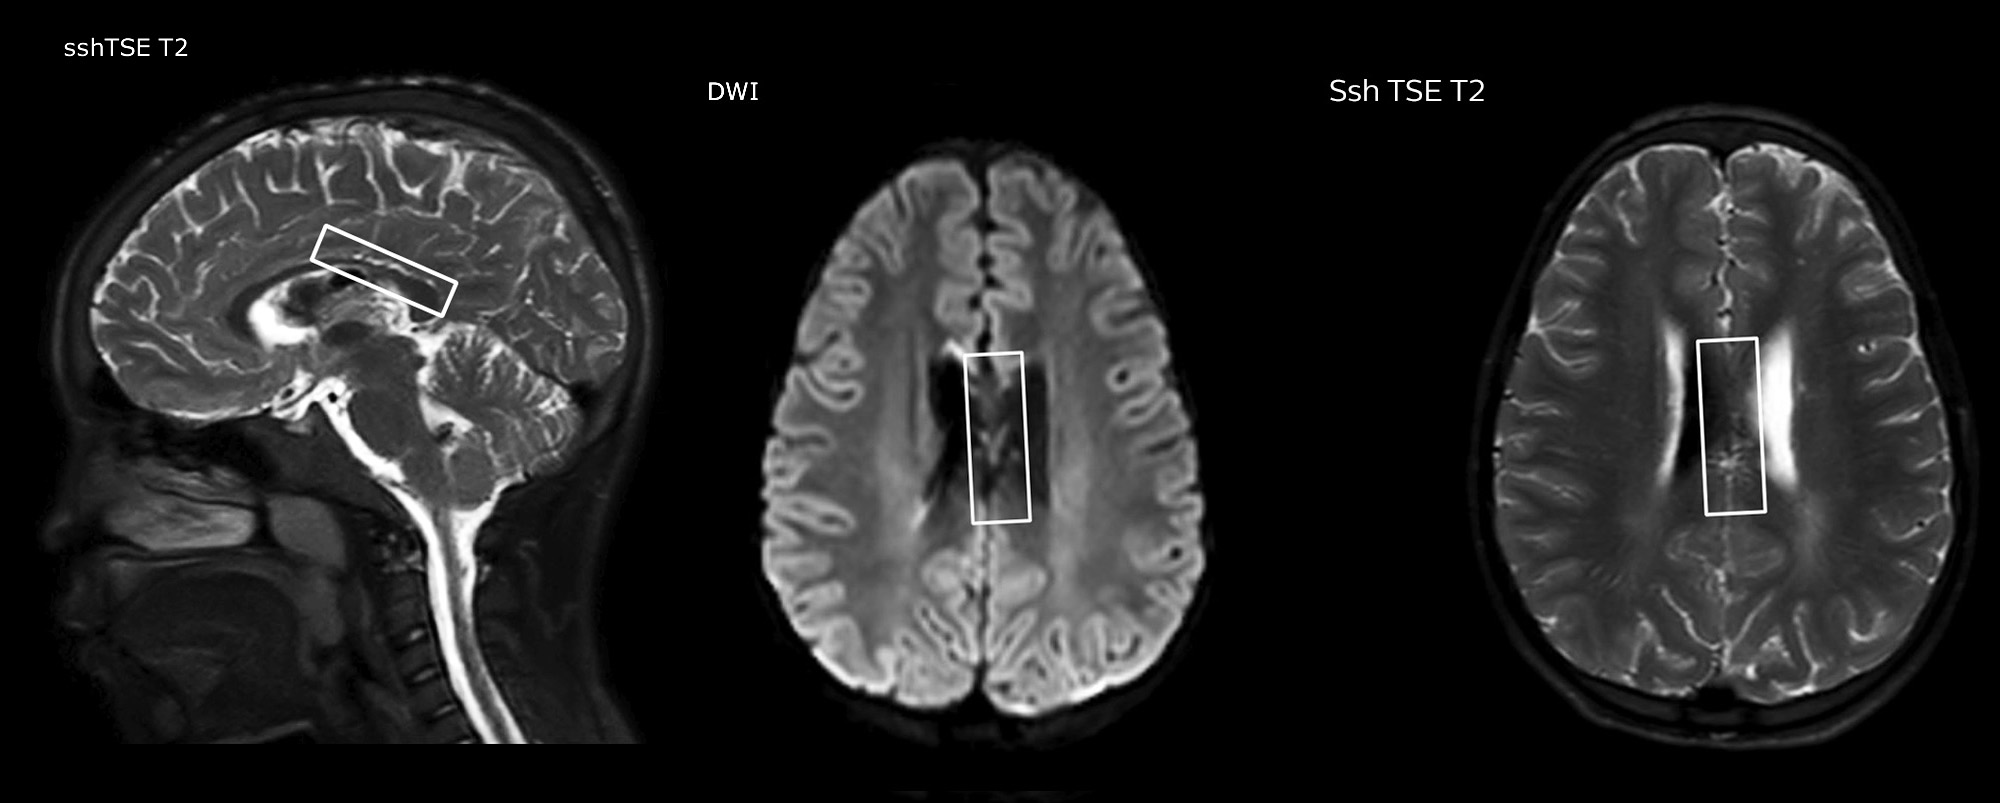

La TSE mDIXON Philips est une technique DIXON à deux points qui sépare les signaux d’eau et de graisse pour une imagerie sans graisse rapide, même dans le domaine complexe de la neuroanatomie. “La TSE mDIXON est l’une des améliorations les plus importantes des séquences d’imagerie que nous utilisions jusqu’alors au PCH”, admet le Dr Miller. “Son acquisition multi-paramétrique nous permet d’obtenir dans la même séquence des images avec suppression de graisse et les images T2 équivalentes sans suppression de graisse. En outre, les anciennes méthodes de suppression de graisse pouvaient être corrompues artificiellement par une anatomie inhabituelle du patient ou par une mauvaise application de l’opérateur. Avec mDIXON, nous disposons désormais d’une méthode efficace et fiable pour supprimer la graisse.” La saturation de la graisse a toujours été difficile aux extrémités du champ d’acquisition, en particulier dans l’imagerie du rachis total et dans les zones anatomiques difficiles, comme les régions inférieures du cou. “Toutefois, grâce aux capacités uniques de suppression de graisse du mDIXON, ces difficultés ne sont plus valables” affirme le Dr Miller. “Nous obtenons quotidiennement une suppression de graisse homogène dans presque toutes les conditions. Cela nous a également mené à un meilleur rendement puisque nous n’avons plus à répéter les séquences à cause des défaillances techniques.”

“La TSE mDIXON a renforcé la fiabilité de nos diagnostics en nous permettant de garder ou d’écarter les anomalies pour lesquelles la suppression de graisse est essentielle au diagnostic, comme les maladies métastatiques ou les anomalies osseuses.”

“La TSE mDIXON est la technique la plus utile chez les patients atteints de lésions ou d’anomalies des tissus mous, par exemple du visage et du cou, et chez les patients victimes d’anomalies de contraste principalement visibles avec la suppression de graisse”, indique le Dr Miller. “Toutes nos imageries du rachis contiennent désormais des images T2 mDIXON avec eau uniquement, ce qui nous permet d’identifier les pathologies potentiellement obscurcies par l’imagerie sans suppression de graisse comme les lésions osseuses. Par ailleurs, il n’est pas nécessaire d’acquérir des images TSE T2 standard supplémentaires car les images mDIXON en phase sont équivalentes aux images TSE T2 standard.”